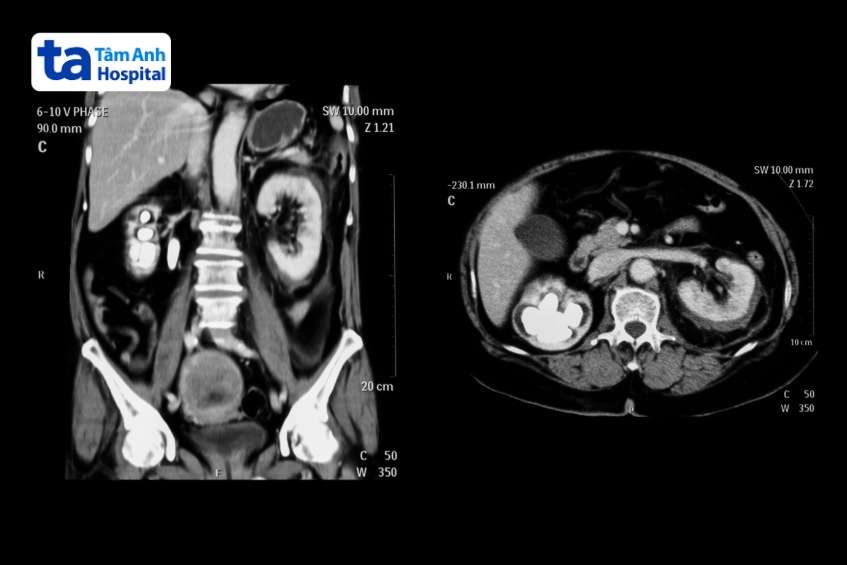

Chụp CT bệnh túi mật là chụp cắt lớp vi tính kết hợp hình ảnh X-quang với công nghệ máy tính để tạo ra hình ảnh chi tiết của túi mật, ống mật, tuyến tụy và gan. Chụp CT có thể nhận diện sỏi mật có kích thước lớn nhất định, phát hiện nhiễm trùng và xác định tắc nghẽn. CT có thể yêu cầu sử dụng chất cản quang để làm nổi bật các chi tiết.

Chụp CT túi mật có thể cung cấp thông tin chi tiết hơn về gan, túi mật và các cấu trúc liên quan so với chụp X-quang bụng thông thường, cho bác sĩ nhiều thông tin hơn về các tổn thương hoặc bệnh lý túi mật…

Chụp CT ở túi mật có thể phát hiện bệnh gì?

Chụp CT gan và đường mật có thể được sử dụng để kiểm tra gan hoặc túi mật và các cấu trúc liên quan để tìm:

Giải phẫu bất thường của hệ thống mật (dị tật đường mật).

Tắc nghẽn ống mật.

Rò rỉ mật hoặc ống dẫn bất thường.

Ung thư hệ thống gan mật.

Nhiễm trùng túi mật (viêm túi mật).

Sỏi mật.

Nhiễm trùng túi mật, ống dẫn hoặc gan.

Bệnh gan.

Giãn túi mật: Khi túi mật bị tắc nghẽn, túi mật sẽ giãn ra và trông giống như một quả bóng bay, căng phồng hơn so với túi mật bình thường.

Thành túi mật dày, không đều: Thành túi mật sẽ trở nên dày, lớn hơn và thường không đều khi có tình trạng viêm. Thành túi mật bình thường là một đường mỏng, sáng khi so sánh.

Tắc túi và dịch: Viêm túi mật cấp tính sẽ dẫn đến tình trạng tắc túi mật và có dịch ở mô mỡ xung quanh do viêm. (4)